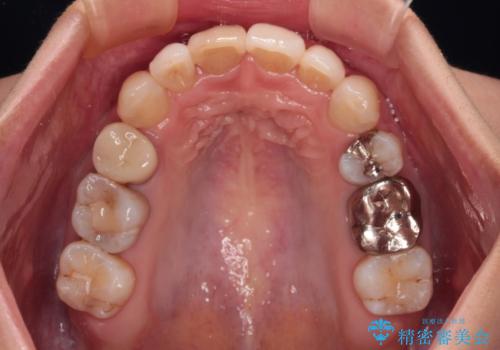

上下の咬み合わせは上顎歯列全体が歯1本分前にずれている状態であり、さらに上顎歯列はV字型に尖っていたため、上下前歯は全く接触していない状態でした。

上顎左右第一小臼歯を抜去して、ワイヤー装置にて口元の突出感を改善するよう矯正治療を行うこととしました。